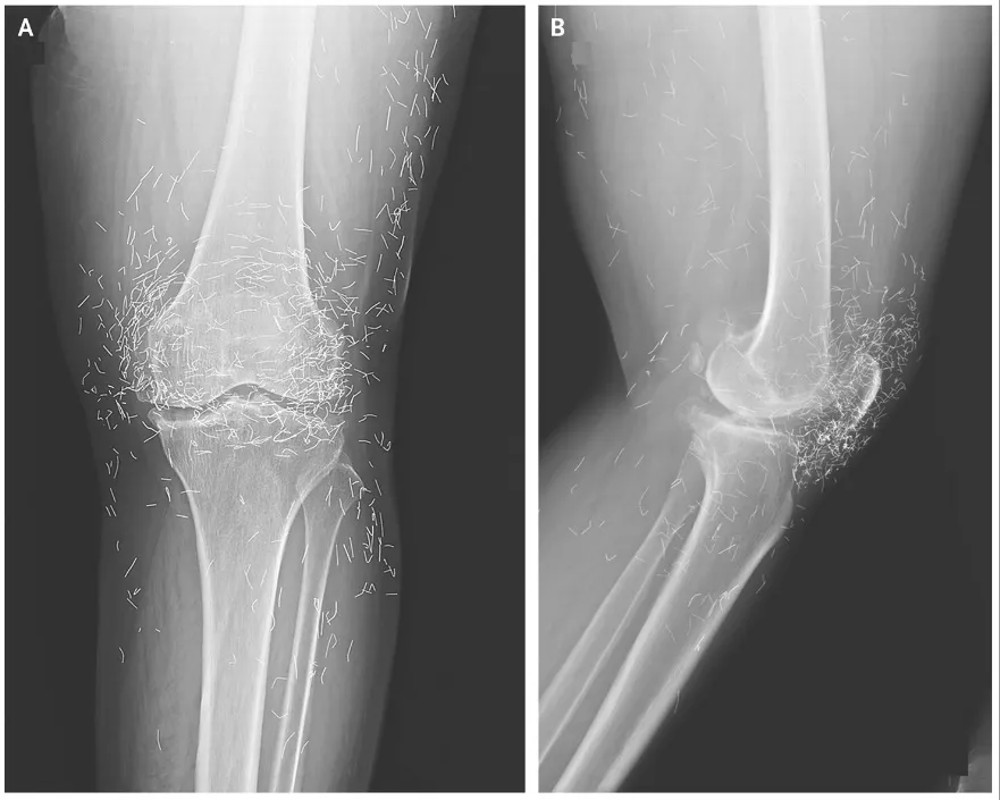

Αργότερα πήγε στο νοσοκομείο επειδή τα γόνατά της πονούσαν πολύ. Οι ακτινογραφίες του αριστερού γονάτου της αποκάλυψαν ότι η κνήμη στο εσωτερικό μέρος της άρθρωσης είχε παχύνει και σκληρύνει. Υπήρχαν επίσης οστέινες αναπτύξεις, που ονομάζονται άκανθες, στα εσωτερικά τμήματα της κνήμης και του μηριαίου οστού κοντά στην άρθρωση του γονάτου.

Οι γιατροί είδαν επίσης εκατοντάδες κηλίδες στην ακτινογραφία γύρω από την άρθρωση του γονάτου, οι οποίες αποδείχθηκαν μικροσκοπικές χρυσές κλωστές.

Οι γιατροί έμαθαν ότι τα νήματα είχαν εισαχθεί στο πλαίσιο των θεραπειών βελονισμού της γυναίκας. Αυτά τα κοντά, αποστειρωμένα χρυσά νήματα είχαν αφεθεί σκόπιμα στον ιστό για να παρέχουν συνεχή διέγερση.